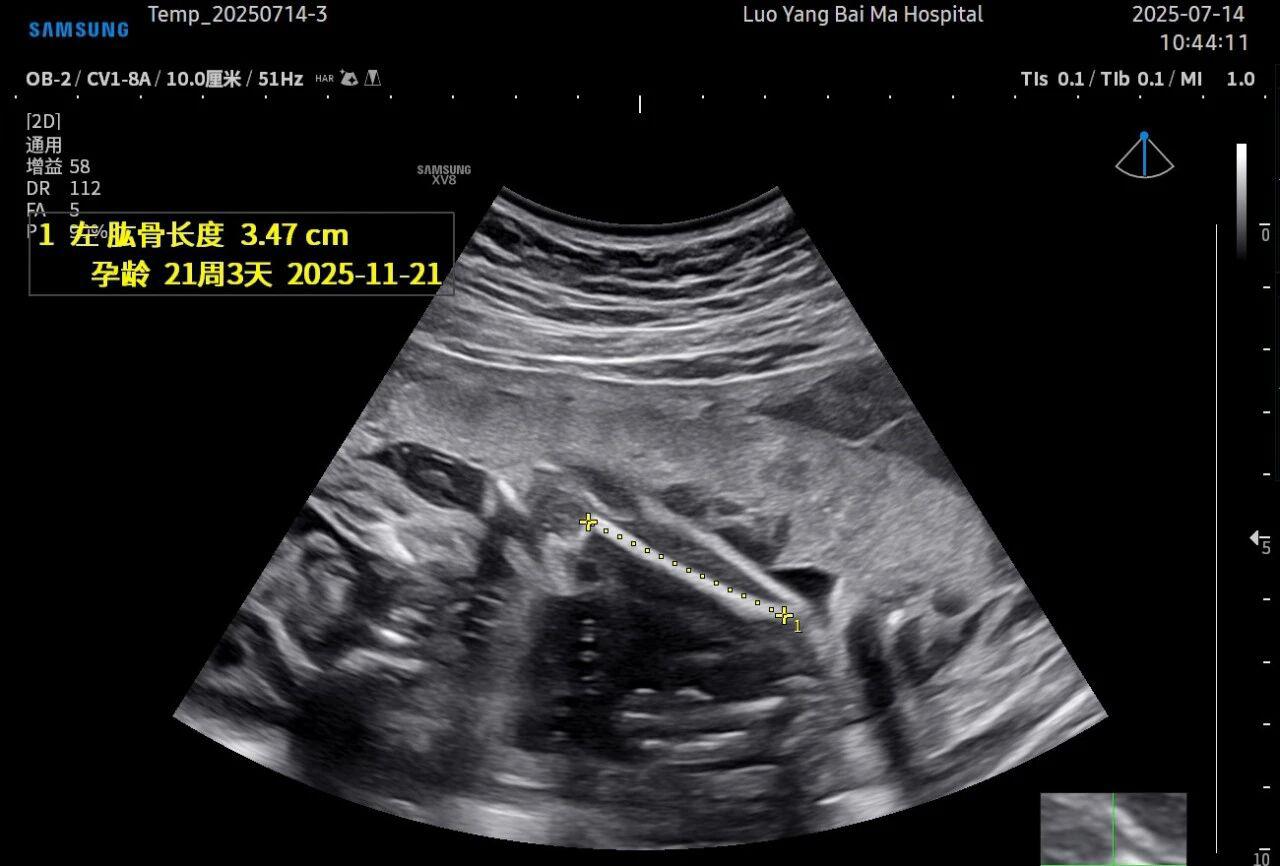

这是5D技术的核心优势之一。系统内置了强大的智能化大数据分析功能和AI辅助诊断工具。例如,在进行胎儿颈项透明层(NT)测量、胎儿长骨(LB)测量等关键生物学指标评估时,5D智能系统可以自动识别解剖层面、智能勾勒测量范围并进行计算。这不仅大大缩短了检查时间,更重要的是,它通过标准化的智能算法减少了因人为操作可能产生的误差,使诊断结果更加客观、可靠。

• 5D彩超检查通常建议在孕20-26周,尤其推荐在孕22-24周进行。此时胎儿大小适中,羊水量充足,图像清晰度较高。